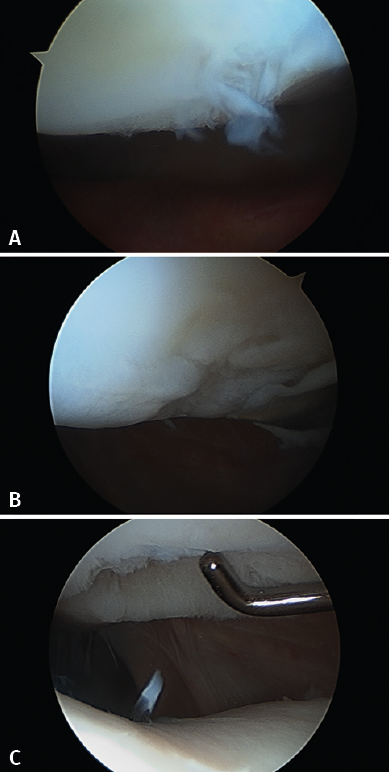

Although cartilage damage is most often of idiopathic or degenerative origin, joint cartilage injuries are also frequently caused by traumatisms (Figure 1A), i.e., joint trauma, followed by osteochondritis dissecans (OCD)(1,2) (Figure 1B).

Although there are a number of classifications for assessing the degree of joint cartilage damage, the most widely used option is the classification of Outerbridge (1961), which defines four grades(5,6) (Figure 3):

• Grade I: softening or edema of the cartilage surface.

• Grade II: fissures or fragmentation affecting a surface of less than 1.25 cm in diameter.

• Grade III: fissures or fragmentation affecting a surface of over 1.25 cm in diameter.

• Grade IV: erosion of the cartilage extending to the subchondral bone.

Figure 4 shows arthroscopic images of lesions corresponding to grade II (Figure 4A), grade III (Figure 4B) and grade IV (Figure 4C).